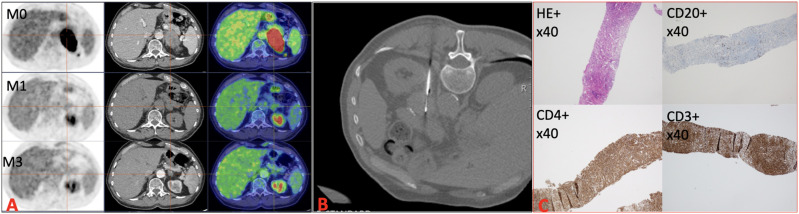

欧洲内分泌学会建议对可疑的肾上腺肿块采取手术治疗,而肾上腺活检的作用有限。我们在此报告了一例 70 毫米肾上腺肿块患者,通过肾上腺活检避免了不必要的肾上腺切除术。一名 80 岁的男性因 67 × 41 毫米的可疑左肾上腺肿瘤接受了检查。激素检测结果正常。18F-FDG-PET/CT 显示肾上腺肿块摄取增加(SUVmax:44.6)。由于诊断结果不确定,于是进行了活检。病理检查发现 T 淋巴细胞炎症浸润,CD4 表型,无恶性标准。经患者同意,多学科会议决定进行简单的密切监测。1个月和3个月后,CT和18F-FDG-PET/CT显示肾上腺肿块的大小和摄取量明显缩小(40×20毫米和19×10毫米,SUVmax分别为5.9和0.0)。该报告表明,对经过严格筛选的病例进行肾上腺活检可避免不必要的肾上腺手术。

The European Society of Endocrinology recommends surgical approach for suspicious adrenal mass with a limited role for adrenal biopsy. We report here a case of a patient with a 70 mm adrenal mass in whom adrenal biopsy avoided unnecessary adrenalectomy. An 80-year-old man was explored for a 67 × 41 mm suspect left adrenal tumor. Hormonal explorations were normal. 18F-FDG-PET/CT showed an increase in uptake of the adrenal mass (SUVmax: 44.6). As the diagnostic was uncertain, biopsy was performed. Pathology found T lymphocytic inflammatory infiltrate with CD4 phenotype without malignancy criteria. Simple close monitoring was decided in multidisciplinary meeting and with the patient's consent. At 1 and 3 months, CT and 18F-FDG-PET/CT showed a significant decrease in size and uptake of adrenal mass (40 × 20 mm and 19 × 10 mm and SUVmax 5.9 and 0.0). This report shows the interest of adrenal biopsy for well-selected cases to avoid unnecessary adrenal surgery.